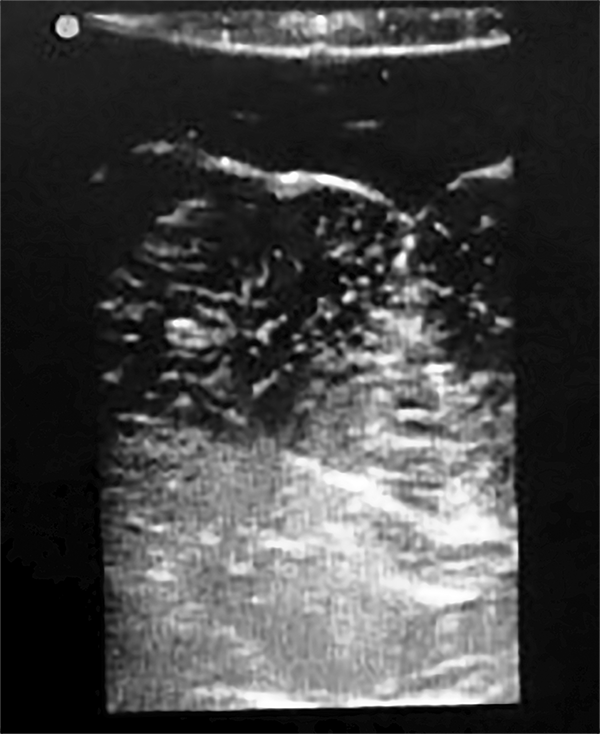

La RMN mostró una lesión tumoral en el hemisferio cerebelos derecho en intimo contacto con los pedúnculos cerebelos medio y superior derecho (fig. 6).

Figura 6: Caso 3. Imágenes prequirúrgicas.